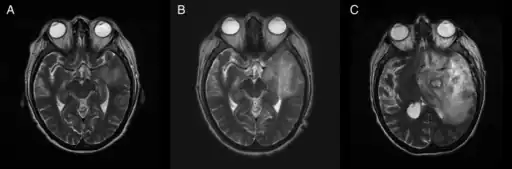

![]() | |

T2-weighted MRI showing liquefied, necrotic brain tissue as a result of GAE caused by an infection of Acanthamoeba, genotype T18 | |